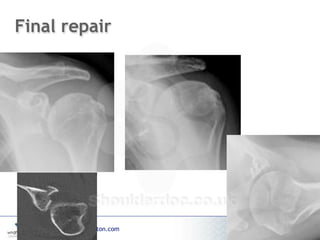

Final repair

www.wrightington.com

Sugaya Technique